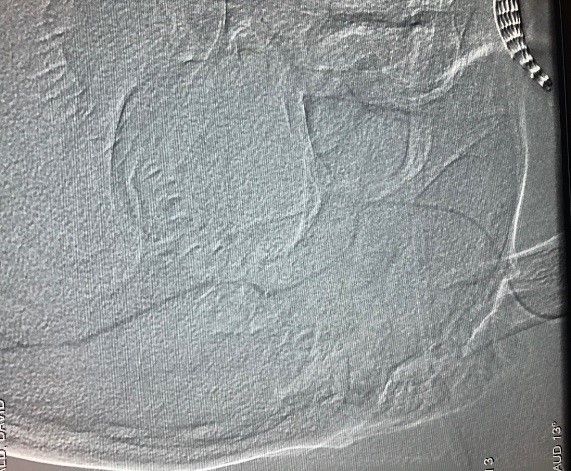

Stroke Imaging Comparison

Previous Imaging for Stroke Care - Munson Healthcare

Previous Imaging